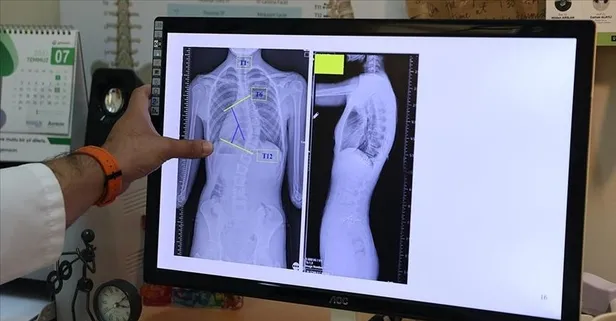

Skolyoz, omurganın bir yana eğrilmesi anlamına geliyor. Doğuştan oluşabileceği gibi, ergenlik döneminden sonra da ortaya çıkıyor. Ortopedi ve Travmatoloji Uzmanı Doç. Dr. Hüseyin Sina Coşkun, hastalığın erken tespitinin tedavide başarı şansını artırdığını belirtiyor. Hastalığın bir tarafta omuzda yükseklik, çocuğun gövdesinde asimetri, bel çukurlarında bir tarafta silinme, bir tarafta daha belirginleşme gibi şikayetlere yol açtığını ifade ediyor.

Skolyoz hastalığında farklı tedavi yöntemlerinin olduğunu belirten Doç. Dr. Coşkun, şöyle devam ediyor: Tedavisi, 20-25 derecelik açıya kadar genellikle gözlem şeklindedir. Bu hastaları inceler, büyümelerini takip ederiz. Herhangi bir tedavi uygulamayız.

Artış devam eder ve bu eğrilik 25 ila 45 derecelik bir yerde konuşlanırsa o zaman da korse tedavileri önem kazanmaktadır. Korse tedavisi ise eğer çocuk büyüyorsa uygulanan bir tedavidir. Büyümesi tamamlanmış bir çocukta ya da erişkinde korse tedavisi uygulanması uygun değildir.

45 derece üzerindeki belirgin kozmetik kusur başladığında ise artık cerrahi tedavi yöntemleri ön plana çıkar. Eğer açı 70-80 dereceleri aşarsa omurga eğriliklerinde kalp ve akciğere baskı durumu ortaya çıkabilir. Her omurga eğriliği bir iç organ sıkışması ya da rahatsızlığı yaratacak diye bir kaide yoktur. Tedavi olarak posterior füzyon dediğimiz omurganın dondurma işlemi yapıldığı gibi, yine son yıllarda popüler olan iple gerdirme sistemi ile omurganın hareketinin korunmasına izin verilmektedir.